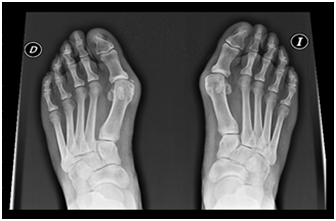

Figure 2 Preoperative Rx showing Hallux Valgus.